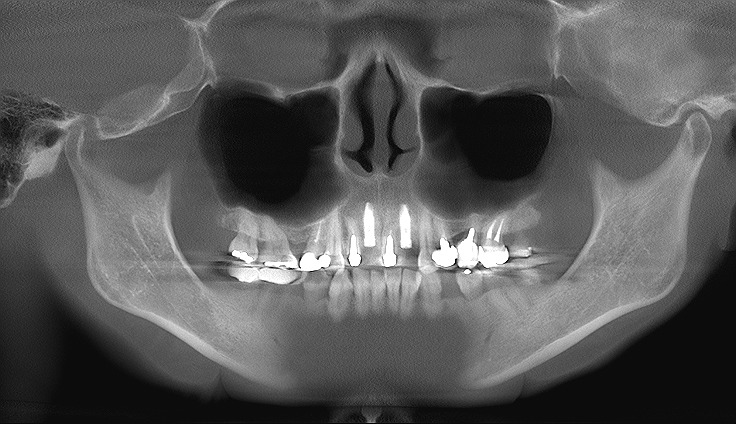

インプラント2本埋入していきました